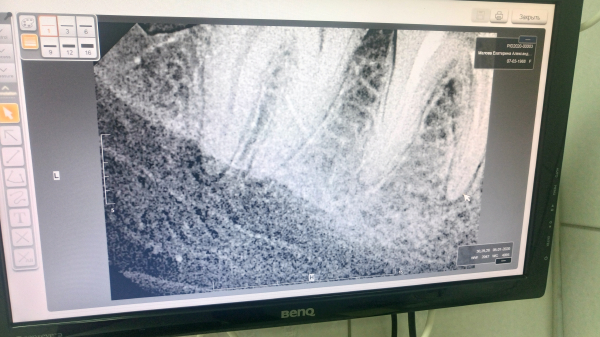

Без клинического осмотра сложно определить однозначно причину. Похоже, в области пролеченного зуба имеется периапикальное воспаление. В области дистального корня соседнего зуба, также определяется разрежение костной ткани. Исходя из снимка, сложно судить, так как возможно наличие артефактов. Причиной онемения может быть воспалительный процесс в области нервных окончаний.